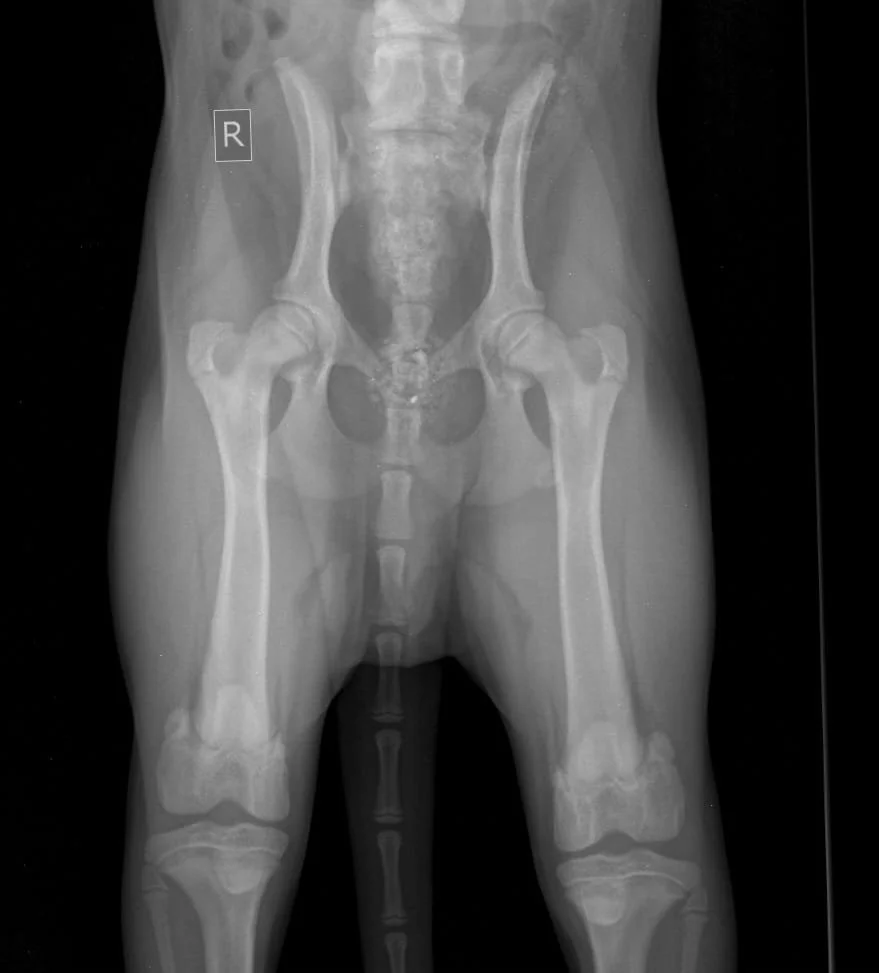

Early Diagnosis of Hip & Elbow Dysplasia in Dogs

Hip and elbow dysplasia are among the most common skeletal orthopedic diseases affecting growing dogs and can significantly impact a dog’s quality of life. They involve malformation of the joints, leading to an imbalanced load distribution within the joint and, consequently, to cartilage erosion, inflammation, and arthrosis.

The first signs of dysplasia can already be detected with certainty at the age of 4 months (5 months in giant breed dogs).

2)      Diagnostic imaging: x-ray under sedation, in some cases combined with CT scan to assess joint conformation minimal joint surface defect (especially in the elbow joint where radiology is indicated for initial assessment but not sensitive enough to confirm the diagnosis).

Large and giant breed dogs are at greater risk to develop dysplasia. For example: the Labrador and the Golden Retriever and their crosses, the German Shepherd, the Rottweiler, the Boxer, the Border Collie, the Newfoundland, the Dogue de Bordeaux, the Cane Corso, and, in general, all molossoids, giant breeds and their crosses.